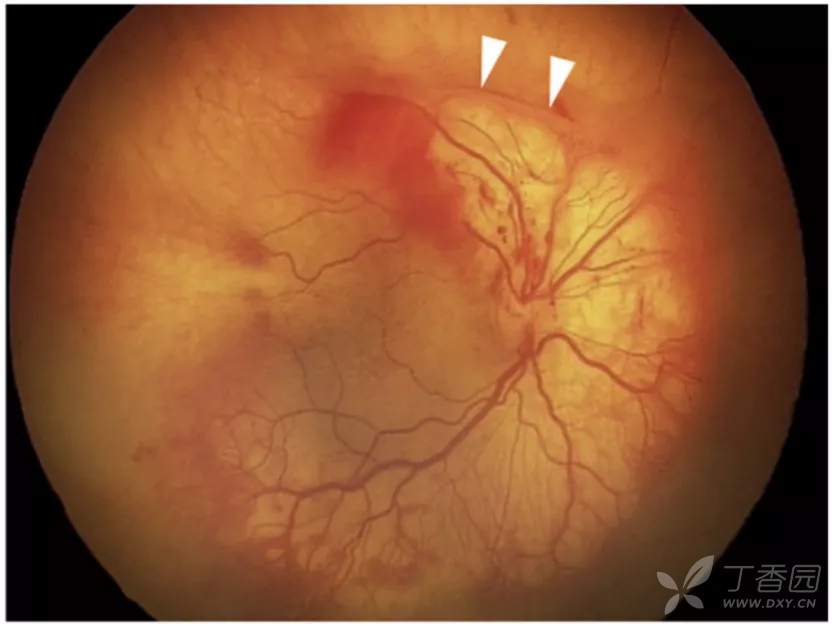

图. 严重plus病变,扁平的视网膜外新生血管伴纤维化,上方收缩(白箭头),视网膜内和玻璃体出血。